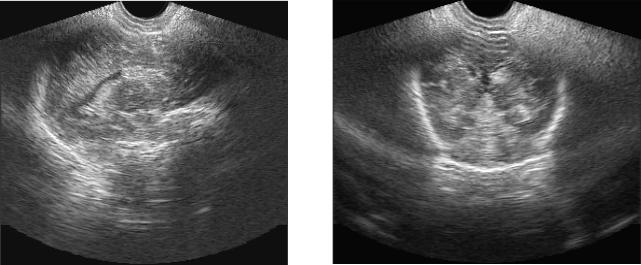

Рис. 8. ПИВК II ст., осложнившееся перивен-

Рис. 9. ПИВК III ст., осложнившееся пери-

трикулярным геморрагическим инфарктом

вентрикулярным геморрагическим инфарк-

(ПИВК IV ст). Боковой желудочек не расши-

том (ПИВК IV ст). Боковой желудочек резко

рен. Зона ярко выраженной гиперэхогенно-

расширен, выполнен кровяным сгустком. Зо-

сти в области переднего рога и тела бокового

на ярко выраженной гиперэхогенности в об-

желудочка.

ласти переднего рога бокового желудочка.